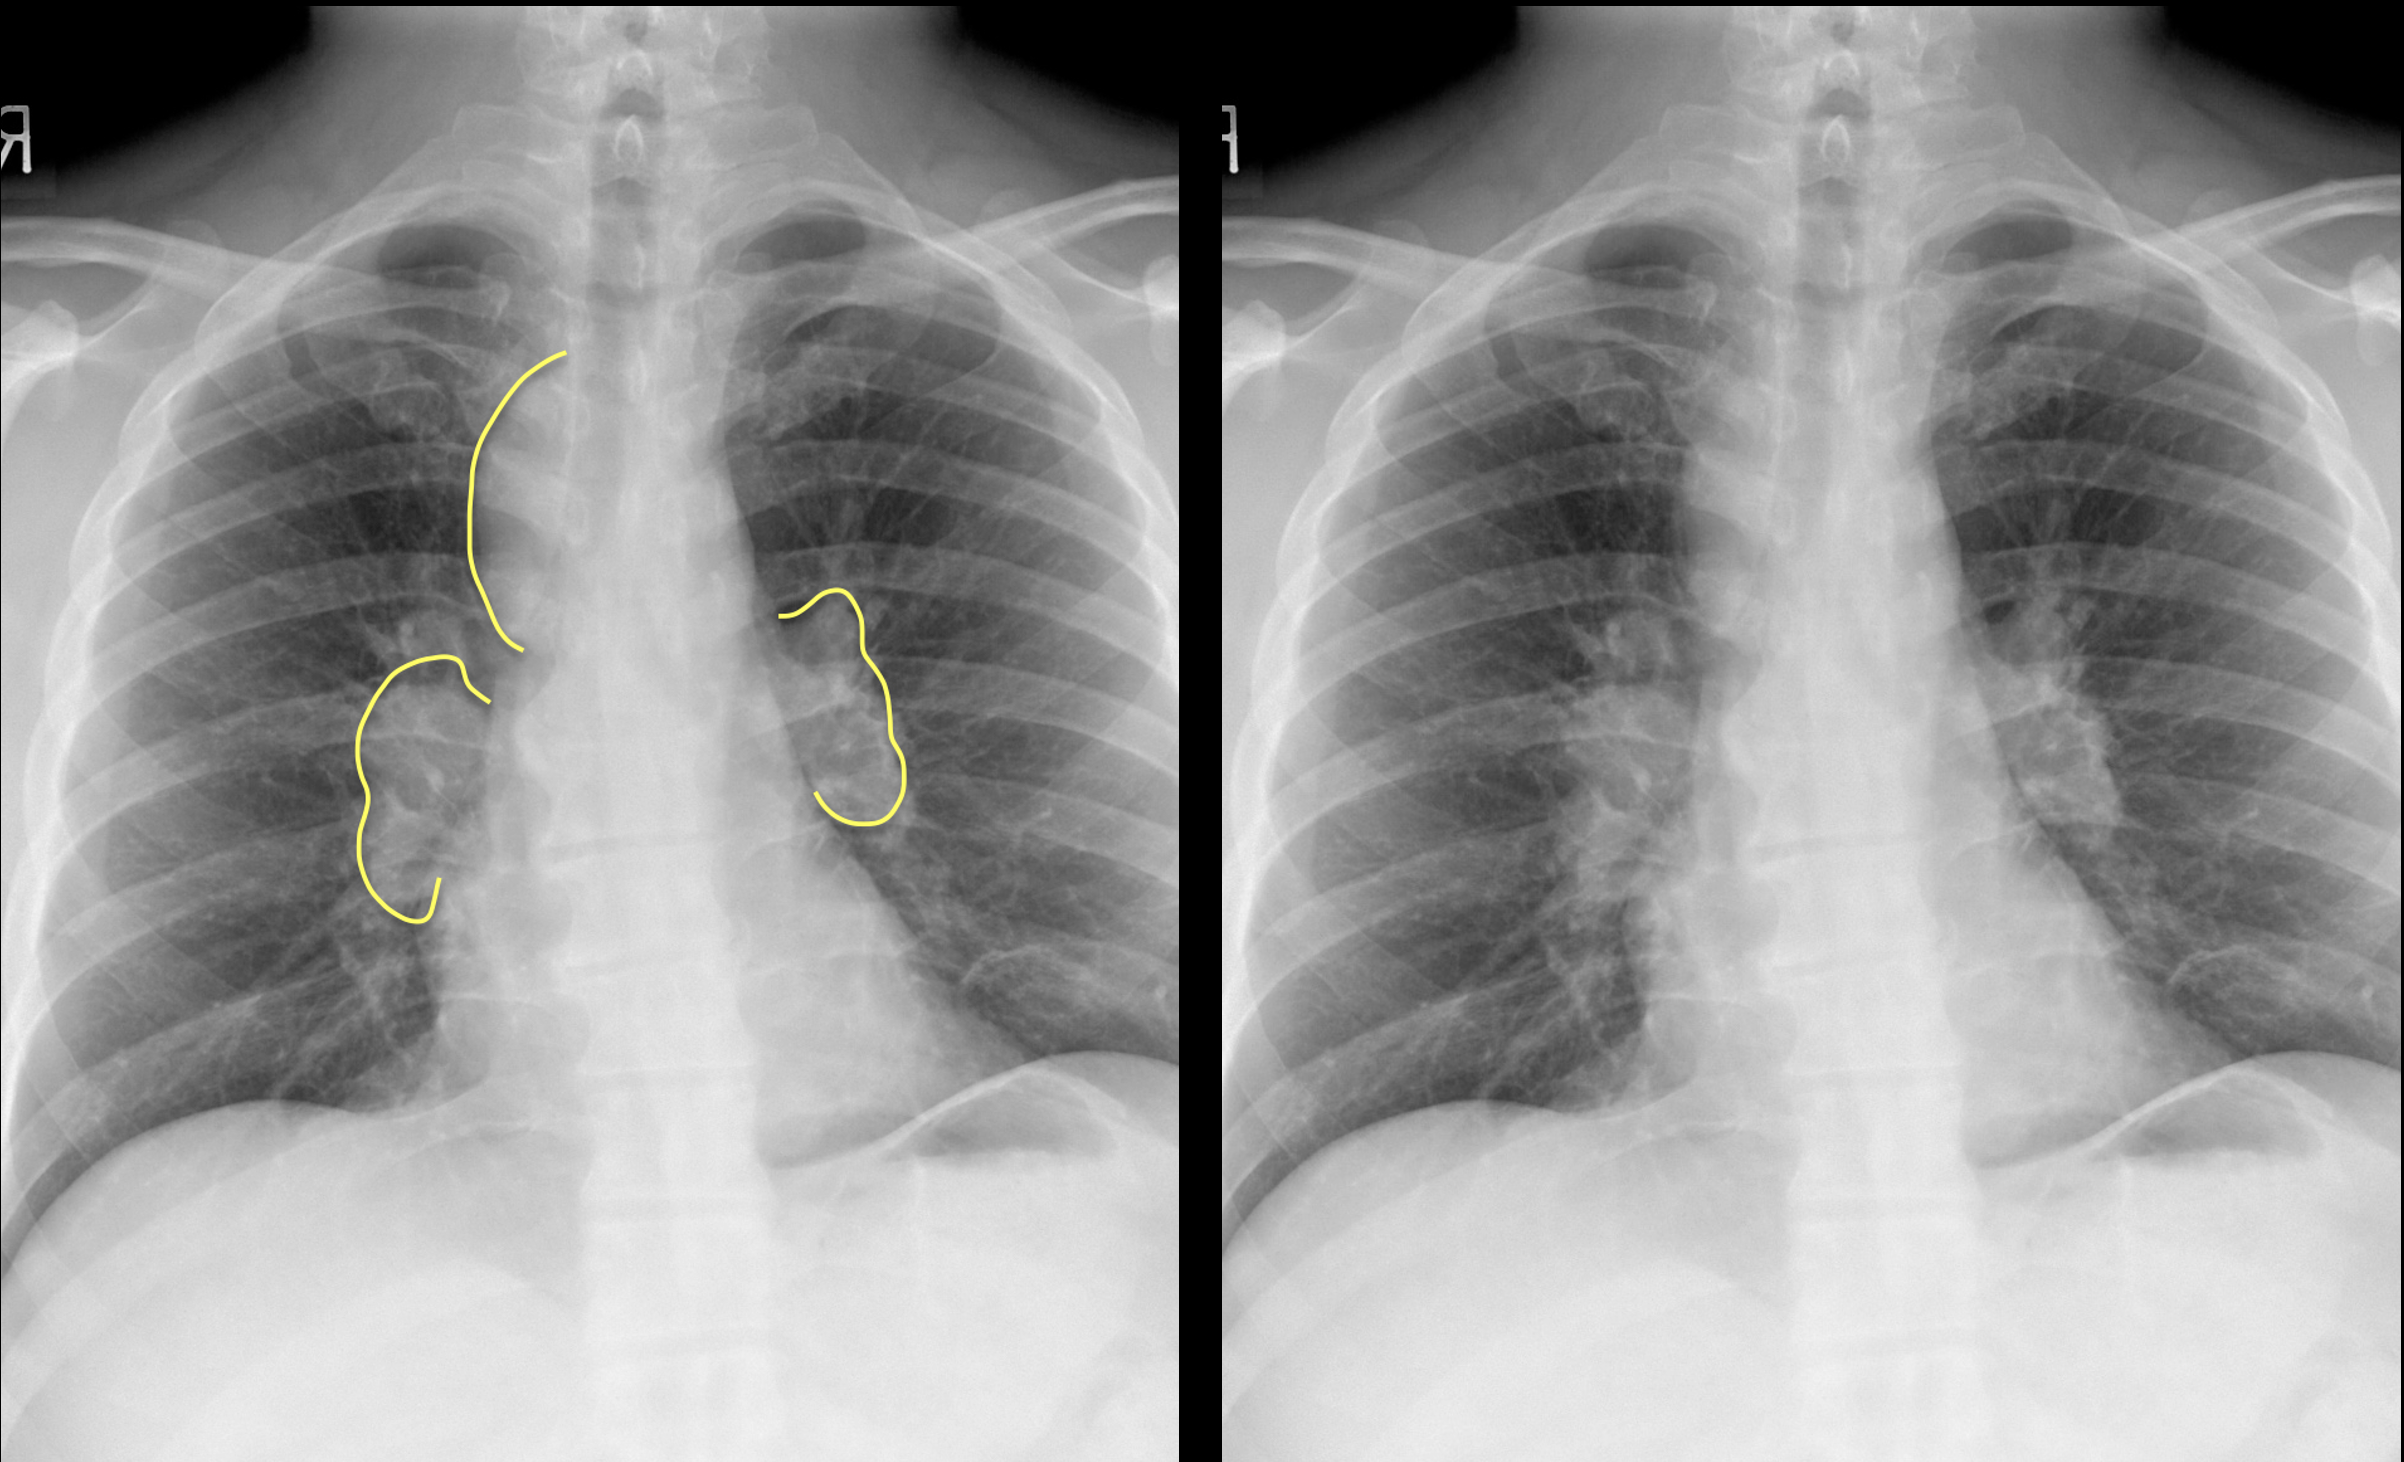

3. Garland's Triad in Sarcoidosis